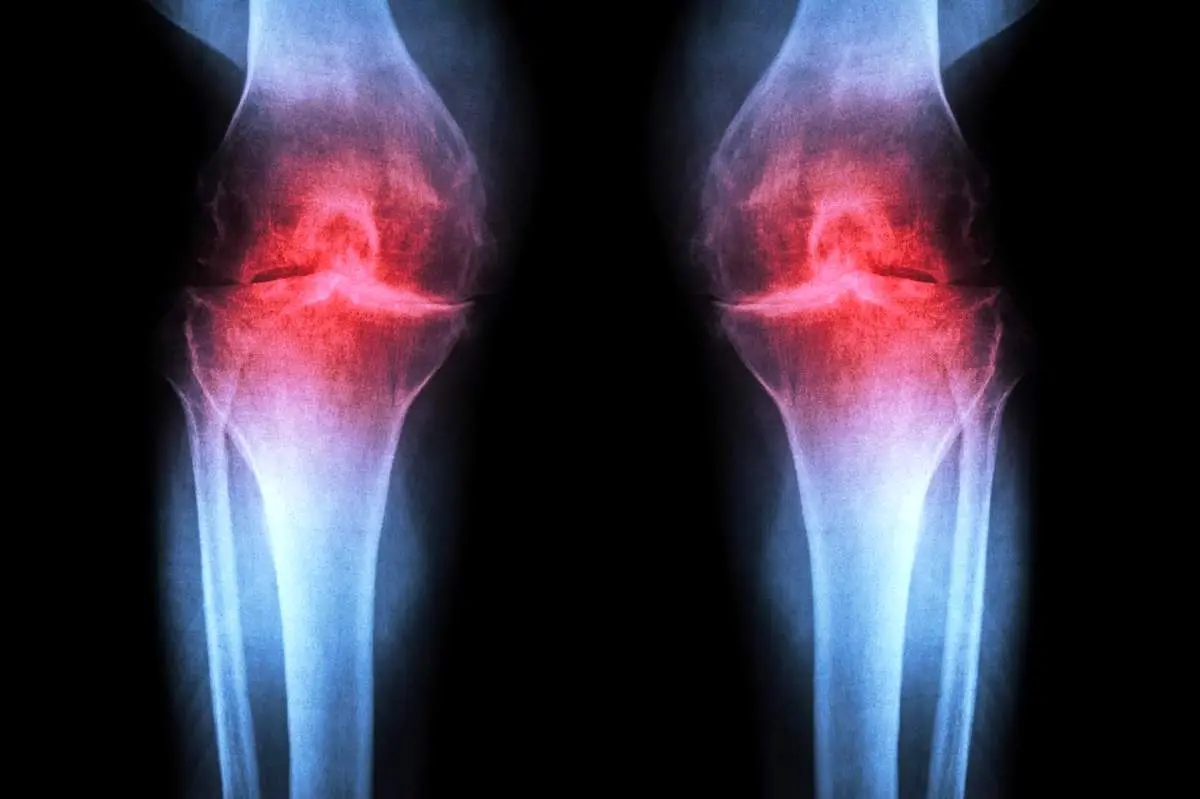

نتایج امیدوارکننده در بافت انسانی؛ آغاز بازسازی غضروف پس از یک هفته درمان

پژوهش تازه در نشریه Science نشان میدهد مهار آنزیم 15-PGDH میتواند غضروفهای فرسوده را بازسازی کند و خطر آرتروز را کاهش دهد. این یافته امیدهای تازهای برای درمان آسیبهای زانو و بازگرداندن عملکرد طبیعی مفصل بدون نیاز به سلولهای بنیادی ایجاد کرده است.

این درمان بهجای کاهش علائم، علت اصلی آرتروز را هدف قرار میدهد. آرتروز یک بیماری تحلیلبرنده مفصل است که حدود یکپنجم بزرگسالان آمریکا را درگیر میکند و سالانه حدود ۶۵ میلیارد دلار هزینه مستقیم درمانی ایجاد میکند. در حال حاضر هیچ دارویی قادر به توقف یا معکوس کردن این بیماری نیست و مدیریت درد و تعویض مفصل، تنها گزینههای درمانی موجود هستند.

آرتروز زمانی رخ میدهد که مفصل بر اثر پیری، آسیب یا چاقی تحت فشار قرار گیرد. کندروسیتها مولکولهای التهابی آزاد میکنند و کلاژن — پروتئین اصلی ساختاری غضروف — را تجزیه میکنند. با از دست رفتن کلاژن، غضروف نازک و نرم میشود و التهاب ناشی از آن باعث درد و تورم مفصل میشود. در حالت طبیعی، غضروف مفصلی تقریباً هیچگاه بازسازی نمیشود.